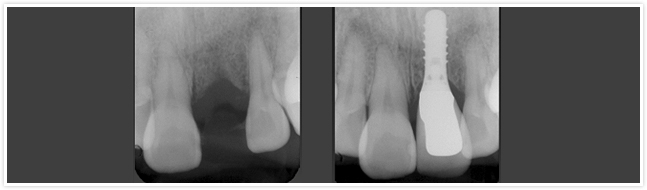

| 奥歯を連続して失った時は…(○歳・女性) |

術前

術後